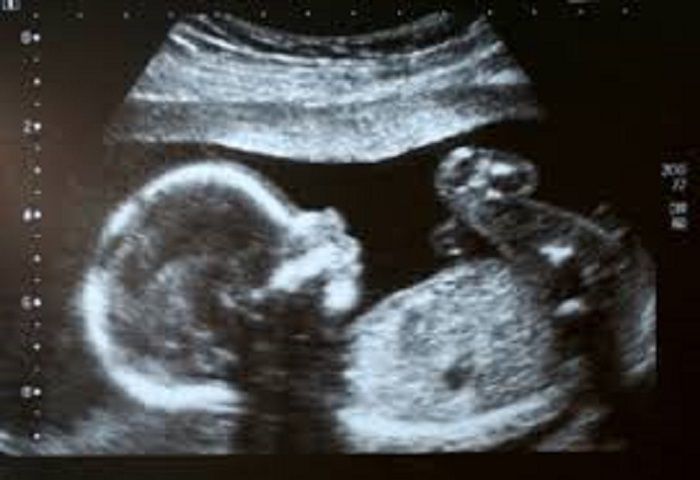

- سونوگرافیNT (nuchal translucency)استاندارد

زمان انجام غربالگری سه ماهه اول، شروع هفته 11 تا 13 هفته + 6 روز بارداری است.

- از آنجايی كه غربالگری آزمايشگاهی در بارداريهای دو قلويی از صحت تشخيصی كافی برخوردار نيست،بهره گيری از مجموع داده های سن مادر و ضخامتNT،در غربالگری دوقلويی توصيه می شود.

صرف نظر از نتيجه مثبت يا منفی غربالگری سه ماهه اول، آزمايش آلفافيتوپروتئين(AFP)برای غربالگری نقص لوله عصبی جنين و سونوگرافی هدفمند هفته 16 تا 18 بارداری برای غربالگری ناهنجاريهای اصلی (ماژور) در خواست می شود.